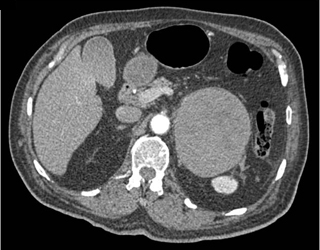

The least likely diagnosis in this case is

adrenal carcinoma

adrenal lymphoma

adrenal metastases

adrenal hematoma